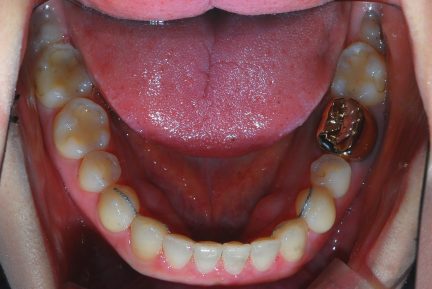

Classe III, articulé postérieur, arcades étroites, arcades asymétriques, déviation de la ligne médiane mandibulaire, décalage de la ligne médiane, rotations, espacement

- Une expansion précédente du maxillaire a été effectuée.

- Après l'expansion, ce cas a été préparé pour la chirurgie orthognatique.

- Seul Invisalign sans autre appareil et sans besoin d'élastiques a été utilisé pour la préparation.

- La dent 1,7 a été extraite car elle n'avait pas d'antagoniste et le patient ne souhaitait pas poser d'implant dans la région de 4,7

État initial